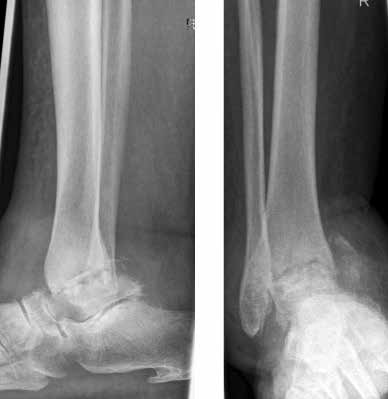

Arthrose stellt weltweit die häufigste Gelenkerkrankung dar und hat damit einen wesentlichen sozioökomischen Einfluss 1. Während 15 % der weltweiten erwachsenen Bevölkerung von Arthrose betroffen sind 2, leiden lediglich 1 % der Bevölkerung 3 bzw. 4,4 % der Arthrosepatienten 4 an einer Arthrose des oberen Sprunggelenks (OSG). Circa 80 % der Arthrosen des OSG sind ursächlich als posttraumatisch einzustufen, nur 9 % gelten als primäre Arthrosen. Dies unterscheidet die Arthrose des OSG von Coxarthrose (58 % primär) und Gonarthrose (67 % primär). 13 % treten im Rahmen systemischer Erkrankungen wie rheumatoider Arthritis, Hämochromatose, Hämophilie oder Osteonekrose auf 5 6. Die posttraumatische Arthrose des OSG wird besonders nach in Achsabweichung verheilten Frakturen (Pilon-tibiale-Frakturen, Weber-A‑, ‑B- und ‑C-Frakturen; Abb. 1a), Bandinstabilitäten des lateralen und medialen Bandapparates des OSG (Lig. fibulotalare anterius, Lig. fibulocalcaneare, Lig. fibulotibiale posterius etc.), nach rezidivierenden ligamentären Verletzungen sowie nach Gelenkverletzungen mit Knorpelschaden, „flake fractures“ oder „bone bruise“ beobachtet 7. Daher ist bei den vergleichsweise häufigen Weber-B- und ‑C-Frakturen die osteosynthetische Versorgung mittels Drittelrohrplatte und Zugschraube (Abb. 1b) sowie ggf. Syndesmosennaht mit Implantation einer Stellschraube mit millimetergenauer Reposition essentiell, um langfristig die Funktionsfähigkeit des OSG aufrechtzuerhalten und eine frühzeitige posttraumatische Arthrose zu verhindern 8.

Das besondere Merkmal der Arthrose des OSG ist das relativ junge Alter der Patienten im Vergleich zur Arthrose anderer Gelenke der unteren Extremität, da die meistens zugrunde liegenden Traumata Sportunfälle sind. Zusätzlich werden ein schnellerer Funktionsverlust des Gelenks und eine beschleunigte Progression der Erkrankung bis zum Erreichen des Endstadiums (innerhalb von 10 bis 20 Jahren) beobachtet 9 (Abb. 2a). Negativ beeinflussende Faktoren für die Entwicklung einer Arthrose des OSG sind: Achsfehlstellungen oder angeborene Deformitäten der unteren Extremität, Muskeldysbalance 10, angeborene oder erworbene ligamentäre Fehlentwicklungen, Alter, Geschlecht und genetische Prädisposition 11.

Weiterhin führen Fehlstellungen im Rückfuß zu statischen und dynamischen Überlastungen, da sich bei Varusfehlstellung (Abb. 2a) das Zentrum der Kraftübertragung nach medial und bei Valgusfehlstellungen nach lateral verlagert 47. Die Achillessehne wirkt durch ihren Zug zusätzlich invertierend bei Varusfehlstellung und evertierend bei Valgusfehlstellung auf den Rückfuß ein 48. Möglichkeiten der operativen Therapie sind entweder die einfache Umstellungsosteotomie der distalen Tibia und Fibula als rein supramalleoläre Osteotomie mit dem Ziel einer Überkorrektur des distalen Tibiagelenkflächenwinkels von 3 bis 5° 49 oder die kombinierte Osteotomie an Bein und Rückfuß (Abb. 2b) mit oder ohne Weichteileingriff je nach Topographie der Achsfehlstellung 50. Weitere Möglichkeiten sind die Calcaneusosteotomie, meist als ergänzende Osteotomie nach Wiederherstellung der korrekten Achse (Abb. 2b) im Sinne einer Verschiebeosteotomie, um die Zugrichtung der Achillessehne zu zentrieren, und die Osteotomie der medialen Säule, die bei durch Valgusfehlstellung induzierter Abflachung des medialen Längsgewölbes indiziert sind. Hierbei werden zusätzlich korrigierende Arthrodesen des I. Strahls (Naviculo-cuneiforme-Gelenk, Tarsometatarsalgelenk) oder plantarflektierende Osteotomien (Cuneiforme I oder Metatarsale I) durchgeführt 51.